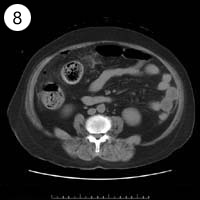

57歳 女性

単純CT

造影CT